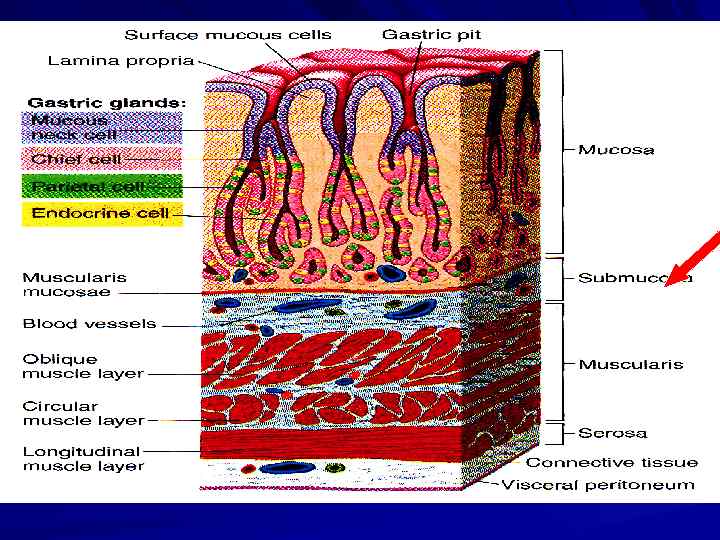

Стенка ПВТ

Стенка ПВТ

МЫШЕЧНЫЕ СЛОИ СЧИТАЯ СНАРУЖИ: 1. ПРОДОЛЬНЫЕ 2. ЦИРКУЛЯРНЫЕ (КОЛЬЦЕВЫЕ) 3. КОСЫЕ (ТОЛЬКО В ЖЕЛУДКЕ)

МЫШЕЧНЫЕ СЛОИ СЧИТАЯ СНАРУЖИ: 1. ПРОДОЛЬНЫЕ 2. ЦИРКУЛЯРНЫЕ (КОЛЬЦЕВЫЕ) 3. КОСЫЕ (ТОЛЬКО В ЖЕЛУДКЕ)